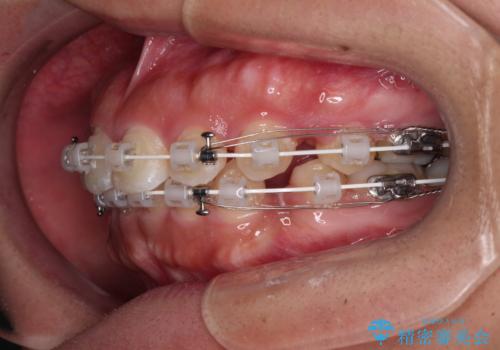

- 口元の突出感を気にして来院された患者様です。

デコボコと口元の突出感が認められたため、上下左右の第1小臼歯4本を抜歯してのワイヤー矯正を行うこととしました。

上顎歯列の横幅が狭く、下顎大臼歯の歯軸が舌側に倒れていたため、急速拡大装置により上顎骨を側方に拡大し、咬み合わせを改善することとしました。

上顎歯列幅を拡大したことで、デコボコを容易に解消することができるようになったため、抜歯により得られたスペースを口元の突出感改善に利用することができました。